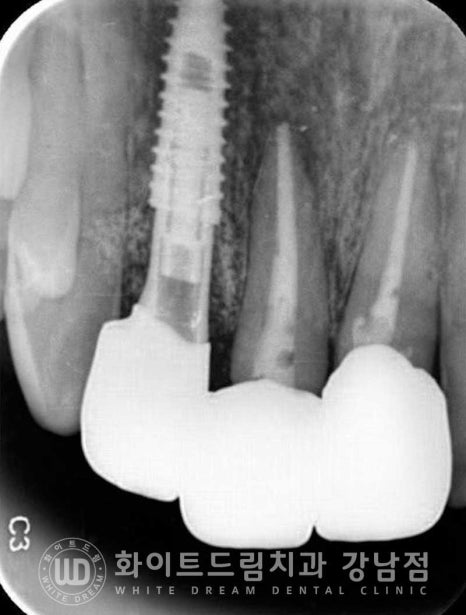

환자분은 초기 11번 치아가 뒤로 물리는 반대교합 형태를 가지고 계셨는데요.

이번에 보철치료를 진행하면서 이 반대교합도 정상교합으로 되돌려드렸답니다.

환자분의 치료 기간은 23.03.16 - 23.08.07으로

5개월 정도의 치료 기간이 소요되었습니다.

치료를 진행하는 과정에서 정기적으로 잇몸치료도 함께 진행해 드려

치료를 마무리하는 시점에는 잇몸상태도 많이 호전된 상태인 것이 확인됩니다.